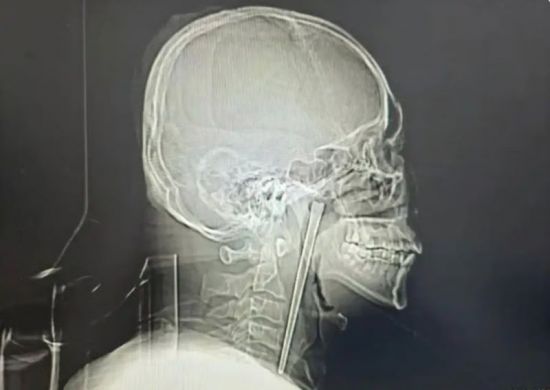

남성의 목에 박힌 금속 젓가락. 바이두 캡처

정밀 검사 결과 A씨가 8년 전 삼킨 금속 젓가락은 입천장 뒤에 위치한 목 안쪽 연구개 부위에 박혀 있었다. 다행히 목 주변 점막은 손상되지 않았고, 성대도 정상적으로 기능했다.